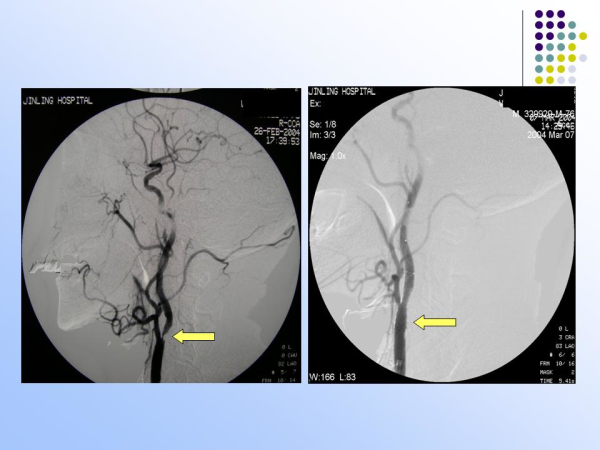

【治疗脑血管病的新技术:血管内介入治疗】—神经内科脑卒中筛查与防治办公室

神经内科

脑卒中筛查与防治办公室